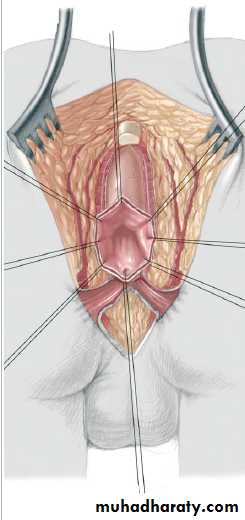

3-4 month later definitive surgery using posterior sagital anorectoplasty(P.S.A.R.P. pullthrogh) Or penna technique.

- Recently laparoscopic pull through using nerve stimulator to identify anal sphincter ,

-the sphincter is not well developed and nerve supply is deficient= continence not good.- 2 months later colostomy closed.